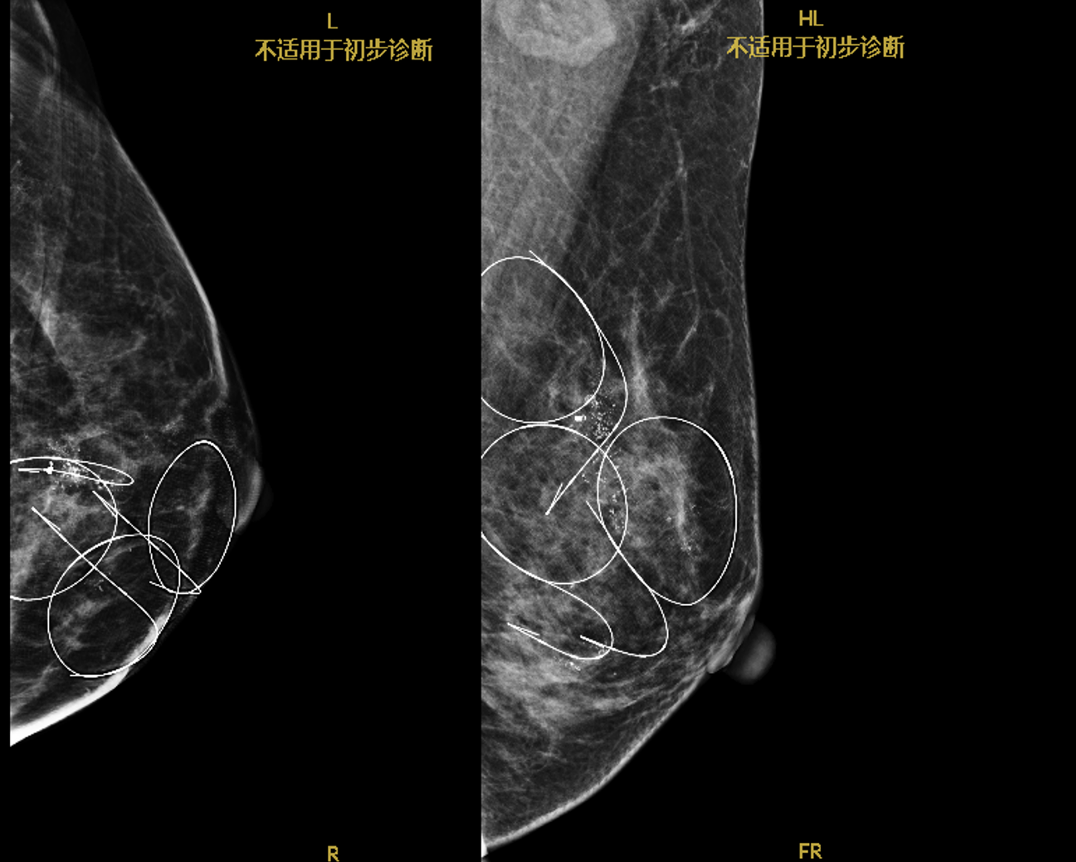

因患者有强烈的保乳意愿,并不愿意行锁骨上淋巴结穿刺活检,要求直接行锁骨上淋巴结清扫,后于治疗约5个月时制定手术方案,并行术前乳腺癌定位夹、乳腺钙化导丝定位。

术前肿物定位夹标记

术前钙化导丝定位

其次,该患者的左乳病灶具有多中心、多灶、广泛钙化的特点,是保乳手术的相对禁忌症。基于综合考量,患者选择行多模态影像引导下的联合多个标记物(marker)定位的左侧乳腺癌保乳根治术+左侧带蒂胸外侧动脉穿支皮瓣缺损修复,以达到多个病灶的一次性、完整地切除,并且在保证切缘阴性的情况下,最大限度地保留了患者相对正常的腺体,最终实现了患者保乳的手术目标。多模态影像技术包括乳腺超声、钼靶及MR检查,三种检查方法相互补充、联合诊断。在上述技术实时监控下,临床医生在不可触及乳腺病灶内植入标记物并联合体表定位实现对乳腺病灶的精准定位或治疗效果监测,以精准切除乳腺病灶,同时保留乳房原有的外形。“多模态影像技术引导下不可触及乳腺病变精准诊疗”的特色新技术,进一步帮助临床突破保乳手术的禁忌症,也是中山大学孙逸仙纪念医院的新的保乳手术特色之一。在本病例中,该特色技术为患者实现保乳的预期,并且有效地、最大限度地保护了正常乳腺腺体,避免了不必要的损伤并降低手术并发症的发生概率。并且,更好地减轻了患者的心理压力,在疾病缓解的同时,也疏导了心理,将“以患者为中心”的理念贯穿于诊疗的各环节。